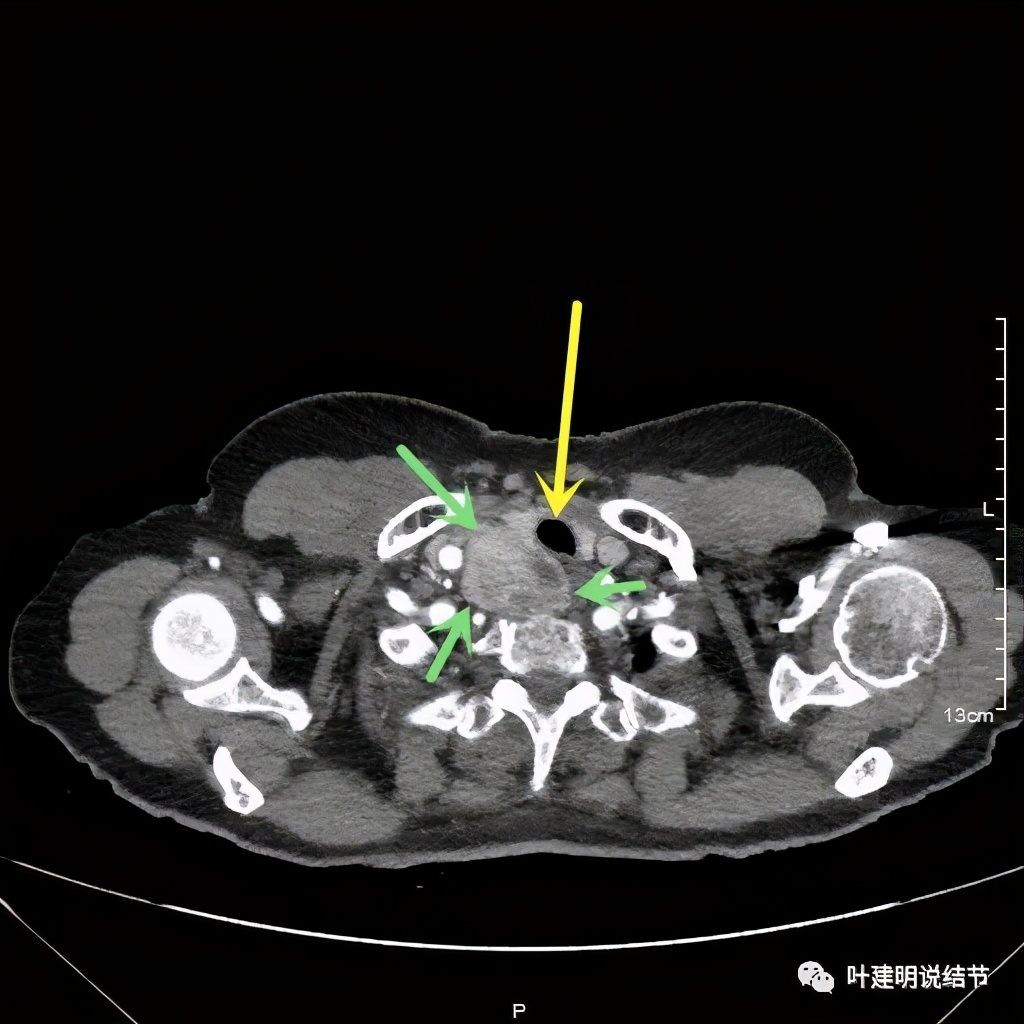

我们由胸顶再往颈部一层一层看,结果真的肿瘤是与右侧甲状腺相连的!那么应该可能是甲状腺来源的纵隔肿瘤(胸内甲状腺肿瘤)。这样的话,其他的边缘界限清楚,这种密度以结节性甲状腺肿可能性大,不太像甲状腺恶性肿瘤。那么与气管间估计也是紧密靠着而已,不会是侵犯的。所以我们商量后就不穿刺,打算直接手术切除。术前做了冠脉CT,也有点问题,好在冠脉狭窄程度不重: